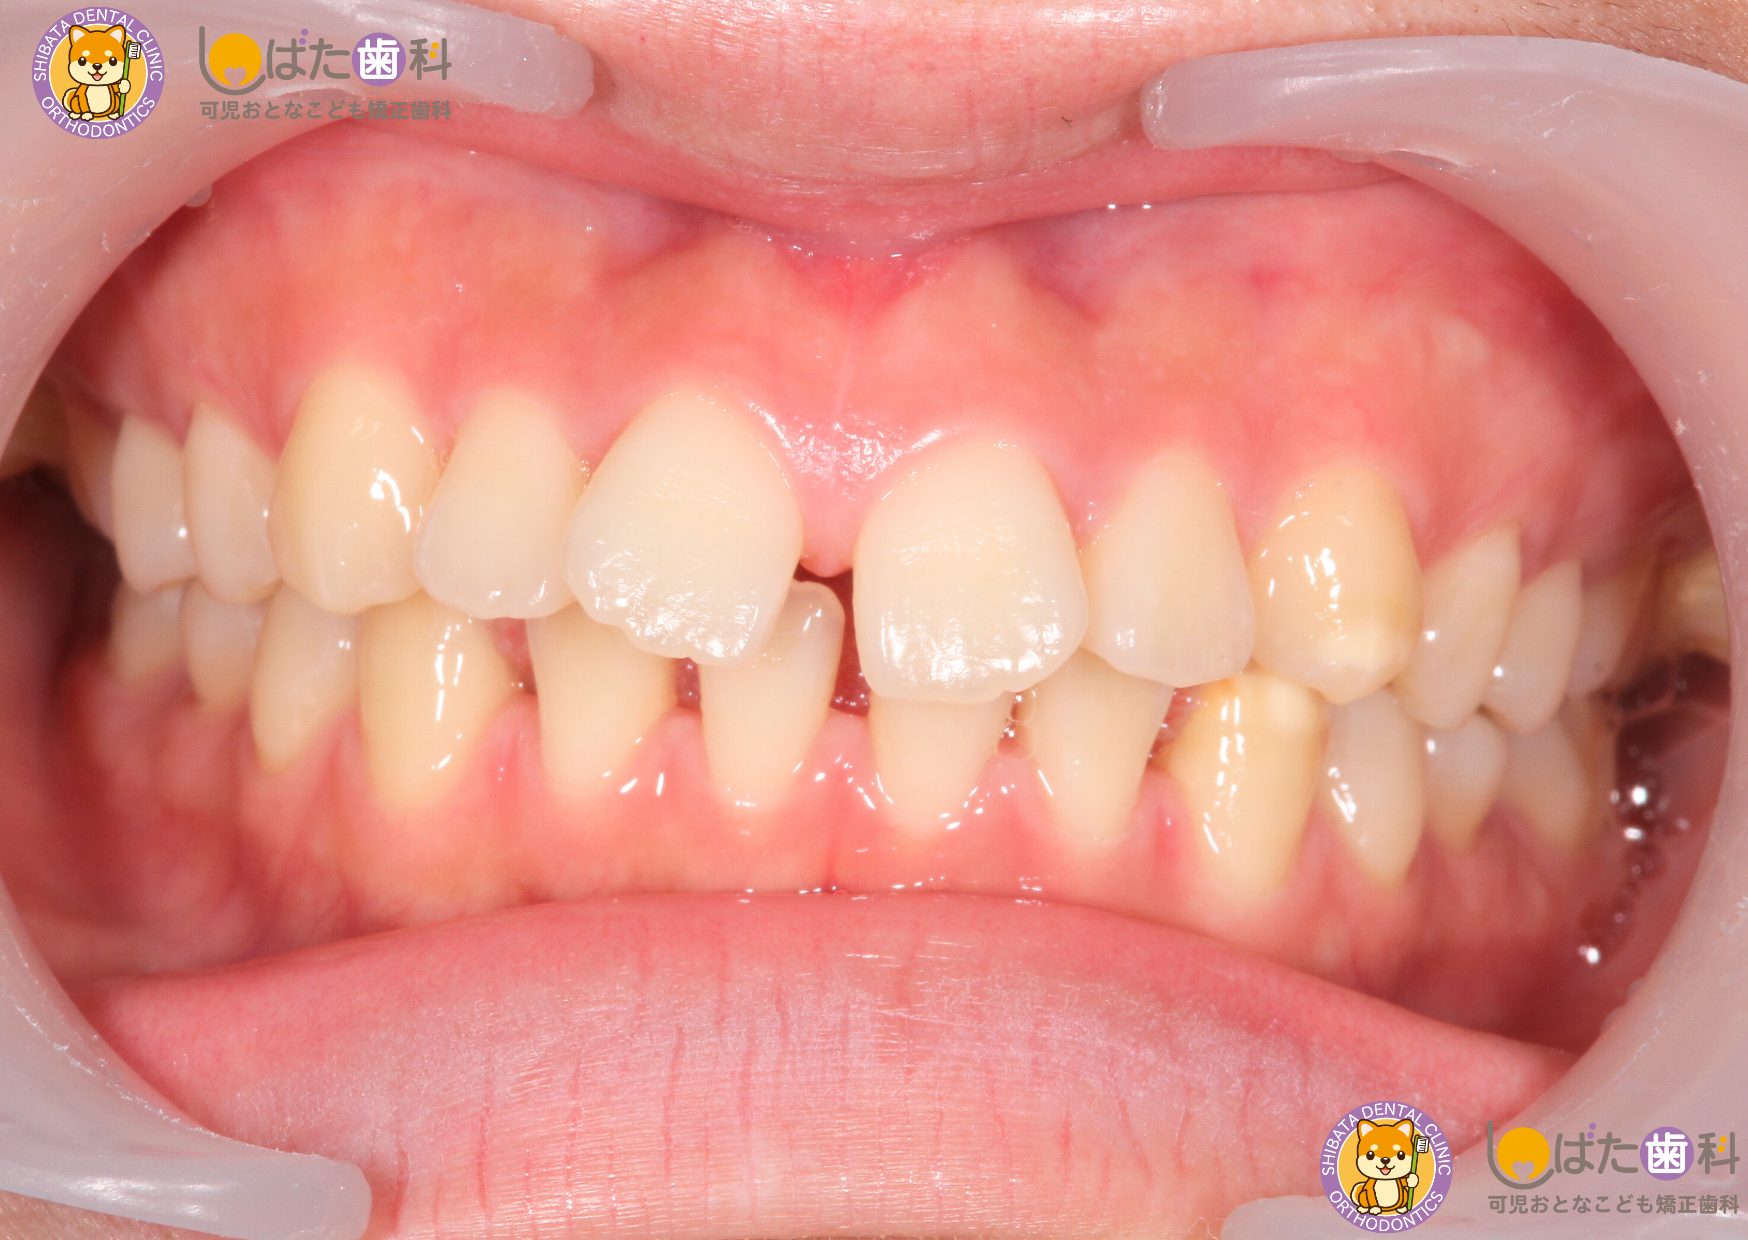

・開咬(かいこう)

開咬とは、前歯が噛み合わず、上下に隙間ができてしまう状態です。指しゃぶりや舌癖が原因で生じることが多く、このまま放置すると永久歯に生え変わった後でも同じ問題が続く可能性があります。